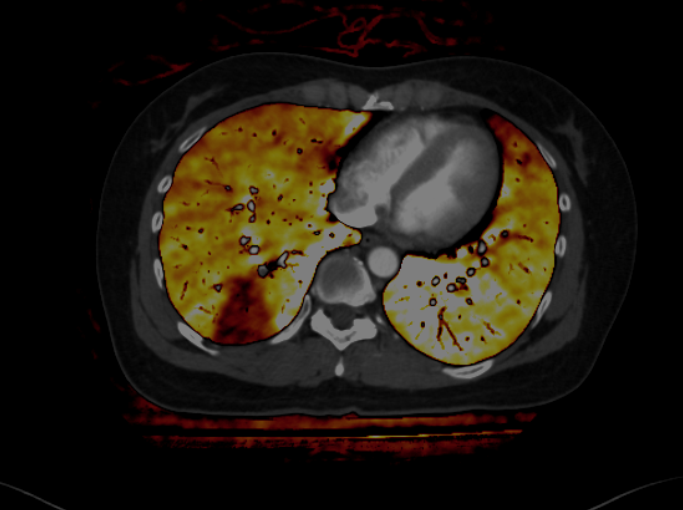

CT 検査(コンピューター断層撮影)

CT 検査とは X 線を回転させながら人体にあて、その情報を検出器で集めコンピューター処理をし、輪切りの写真や様々な方向の断層像を作り出す検査です。頭部、胸腹部、骨などを細かく検査することが出来ます。また脳血管、胸腹部大動脈、心臓・冠動脈などを三次元表示し、様々な角度から観察することもできます。

当院の CT は検出器が多列化した 64 列マルチスライス CT 2 台が稼動しています。従来の CT に比べ非常に高速な撮影が出来るため息止め時間が短く、全体の検査時間も短縮できます。

当院は 2022 年4月、機器更新に伴い新たに SIEMENS 社製 SOMATOM Drive を導入しました。2つの X 線発生装置を搭載しており、従来の CT に比べ非常に高速な撮影が出来るため息止め時間が短く、呼吸停止が難しい場合でも動きによるブレの少ない画像を撮像できます。また、新しい被曝低減技術により、さらなる被曝線量の低減を実現し、今までにない、様々な画像を作成できるようになりました。